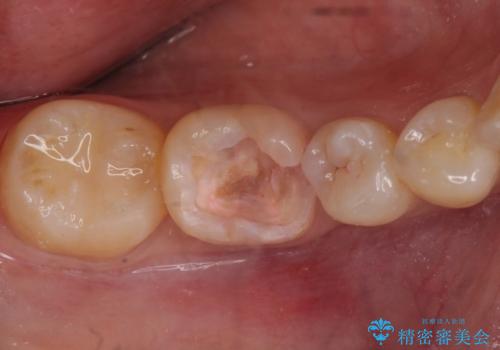

- 右下の奥歯が欠けたとのことで来院されました。

診てみると奥歯の詰め物が欠けていることが分かりました。

噛みしめが強く、元の詰め物の大きさが大きかったため今回は被せ物での治療をすることとなりました。

欠けた詰め物をすべて取り除くと深いところに取り残された虫歯を発見しました。